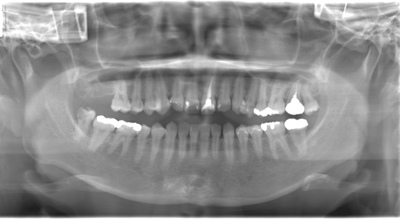

CASE 2

| 年齢・性別 | 30代・男性 |

| 主訴 | 左上下親知らず抜きたい |

| 抜歯期間 | 30分 |

| 抜歯費用 | 約2,500円(保険内) 別途CT撮影で3,000円 |

| 抜歯内容 | 左上下の親知らず抜歯 |

CASE 3

| 年齢・性別 | 20代・男性 |

| 主訴 | 左下親知らず抜きたい |

| 親知らずのはえ方 | 半埋伏 |

| 抜歯内容 | 左下の半埋伏親知らず抜歯 |

CASE 4

基本情報

|---|---|

| 主訴 | 左上親知らず抜きたい |

| 抜歯期間 | 15分 |

| 抜歯費用 | 約2,000円(保険内) 別途CT撮影で3,000円 |

| 抜歯内容 | 左上の親知らず抜歯 |